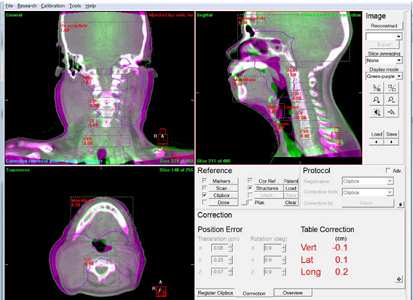

IGRT

IGRTとは、照射の直前や照射中にX線写真やCT画像を取得して、治療計画時の画像と重ね合わせて、骨やマーカーなどをもとに正確に合わせ込みを行い、位置のずれの量を求めて寝台位置の修正を行ってから照射を行います。